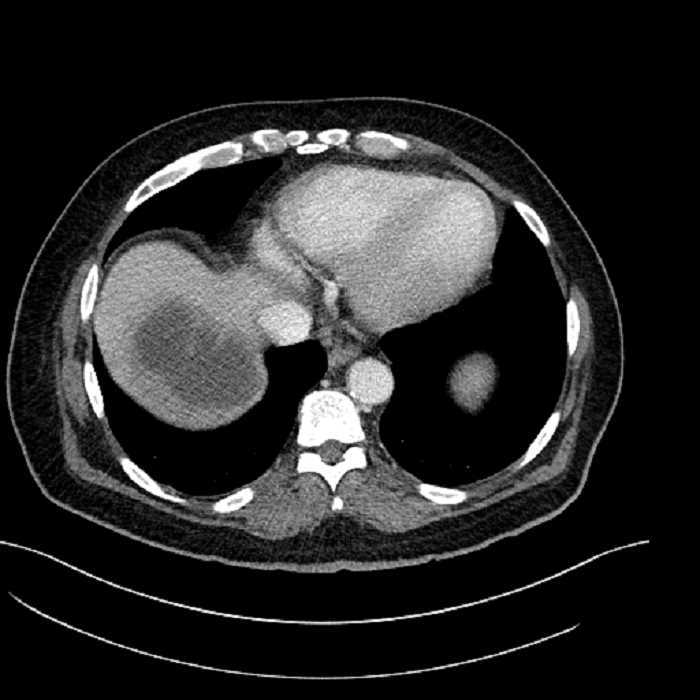

• The classic CT imaging appearance is a double target sign with internal low density surrounded by an internal enhancing rim (capsule) and a low density external rim (edema)

• Abscesses may be unilocular or multilocular

• Gas is present in a minority of cases

Hepatic abscess showing the double target sign with low density internally surrounded by a thin inner enhancing rim (red arrow) and ill-defined outer low density rim (yellow arrow). Blue arrow indicates an internal septation. Red arrows: additional smaller subcapsular abscesses. Red arrow: focal contained perforation associated with diverticulitis.